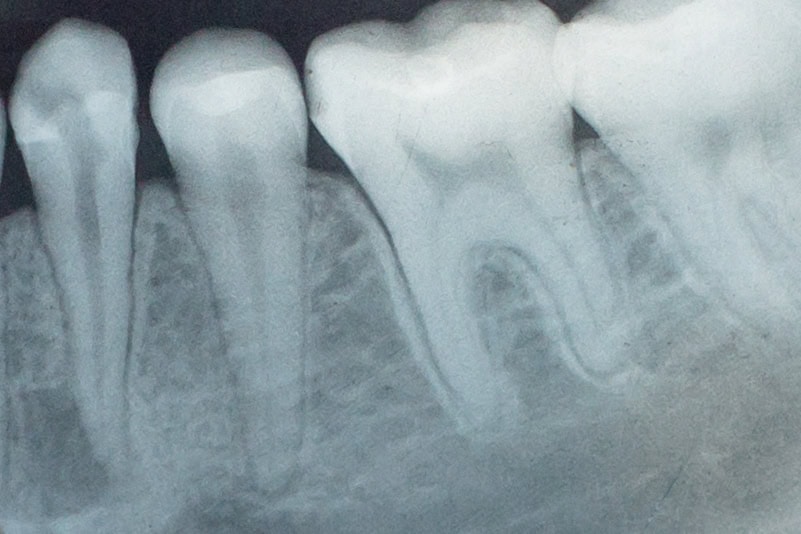

Dental x-rays are a diagnostic procedure that can help to reveal problems that may be invisible to the naked eye. For example, pockets of decay between teeth, bone loss that may be linked to gum disease, abscesses at the root of the tooth and changes in the root canal can all show up on an x-ray.

A dental x-ray can reveal problems that aren’t visible to the naked eye.When do you need a dental x-ray?